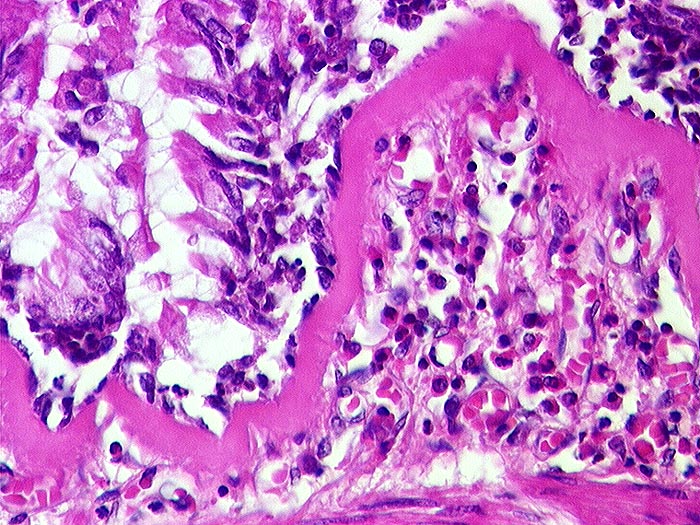

AP/ Asthma bronchiale

Asthma bronchiale

Bronchus

Pathologischer Befund